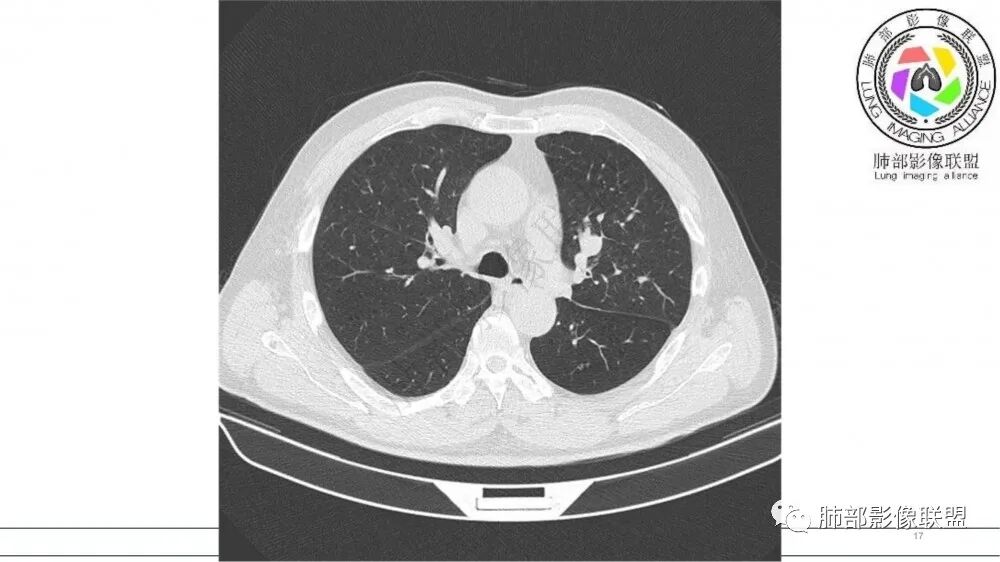

左肺上叶前段支气管杵状指样扩张,内见实性组织阻塞性,并强化明显,边缘饱满,周边多发小斑点影,小花小草征,老年男性,长期吸烟史,方向恶性,首选支气管内浸润鳞Ca可能性大。

老年男性,肺气肿,吸烟史,左肺上支气管腔内铸型高密度影,呈指套状,远端多发树芽,增强不均匀强化,考虑鳞癌,鉴别小细胞癌

B3指套征,常规不是鳞癌就是ABPA,有强化丶血管造影征,倾向于鳞癌

老年男性,吸烟史,左肺上叶支气管塑形生长肿块,整体边缘较圆钝,不均匀强化,血管走形,形态较纤细,病灶远端可见花草样改变,恶性,先考虑小细胞癌鉴别鳞癌

老年男性,长期吸烟史。左上肺前段沿支气管走形的指套样病变,增强可见病灶强化(排除结核、ABPA(也无气喘症状)),远端多发点状高密度影。考虑恶性肿瘤,鳞癌可能性大。

老年男性,吸烟,指套征,蠕虫征,阻塞性炎症不严重。可见血管穿行,密度均匀,轻度强化,首先考虑小细胞肺癌。鉴别鳞

指套征:是影像征象,胸部平片表现为手指状密度增高影,以肺门为中心呈放射状分布,CT显示扩张支气管内低密度黏液栓形成或实性病变,呈管状、树枝状或卵圆形密度增高影;支气管扩张伴近端梗阻时,扩张支气管内部黏液分泌物不能排出而形成。可以伴随远端空气潴留征、阻塞性炎症。

研究报道,中心型 SCLC 经 CT 扫描后通常支气管表现为鼠尾样狭窄,肺门或纵隔肿块明显,由于肿块沿管壁生长表现为顺延支气管形态的不规则形状。病灶相对特征性影像学表现比如鸭蹼状、腊肠状、葫芦状及葡萄状改变,可以出现血管包埋,很少有空洞、空泡,较少引发肺不张,阻塞性炎症成都较轻。与一般肺癌比较,恶性程度高,侵袭力强、病灶很小就容易远处转移!Herzberg 等[19]研究指出,20%以上 SCLC 倍增时间短,预后不良。